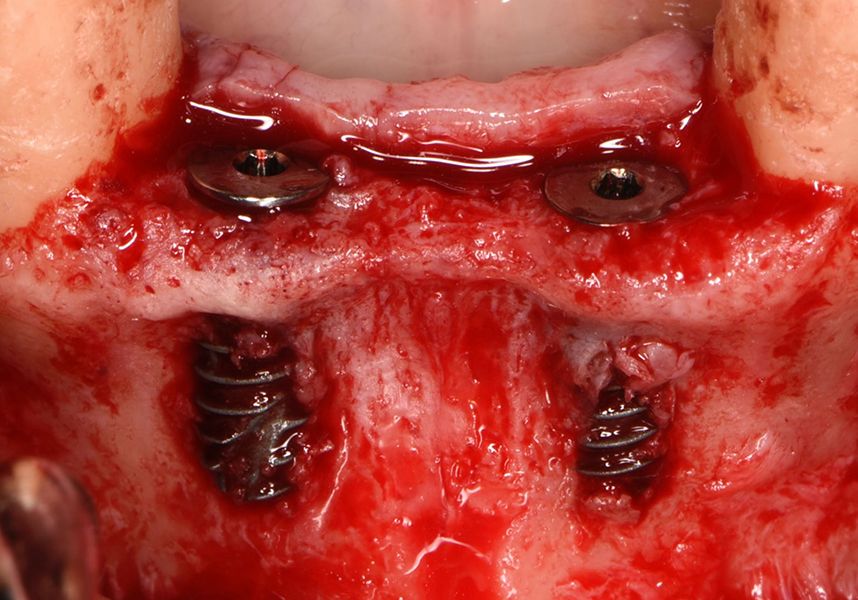

Placement of two dental implants was considered in the anteroinferior area, with simultaneous guided bone regeneration during the same surgery and the subsequent delayed placement of a metal-ceramic bridge for four teeth from 42 to 32. In addition, it was planned to insert three implants in positions 46, 34 and 36, also for restoration with metal-ceramic prosthesis.

The patient was anesthetized and a flap was made from the distal area of tooth 43 up to 36. Then two Avinent Biomimetic Ocean IC implants of 3.5x10 were inserted in positions 32 and 42.

Respecting the three-dimensionally correct position of the implant led to bone fenestration, leaving the apical part of the apex of the implant exposed almost to the mid-point of its length at 42 and a third in 32.

In the posterior sector three Biomimetic Ocean IC implants of 4.0x10 were inserted in positions 36, 34 and 46 with delayed load. A small regeneration was also carried out with autologous bone in the implant in position 34, where there was no exposure, but the vestibular cortical was very fine after implant insertion.